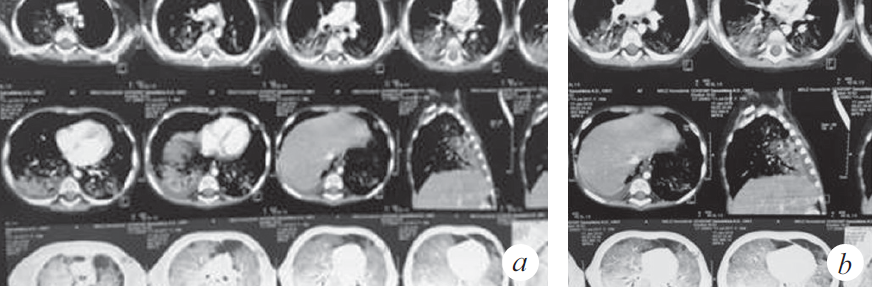

Продуктивный кашель с затрудненной эвакуацией мокроты впервые появился 12.12.2018, нарастала дыхательная недостаточность (одышка, кислородная зависимость), клинически и рентгенологически диагностирован спонтанный пневмоторакс справа (купирован дренированием). Во время дренирования развилась депрессия сердечной деятельности с переходом брадикардии в асистолию, с восстановлением ритма в течение 1 мин. после однократного введения адреналина и закрытого массажа сердца (15 с). Ребенок был переведен на искусственную вентиляцию легких (ИВЛ) (респиратор Savina, Dräger, Германия), отмечалась потребность в FiO2 0,6 для поддержания SpO2 92–95 %. Параметры вентиляции: SIMV, MV 6–7 мл/кг, PIP от 20 до 22 мбар; PEEP (режим BiPAP): минимум 4 мбар, максимум 8 мбар. На следующий день выполнена нижняя трахеотомия и установлена трахеостомическая канюля. Пациентка находилась на ИВЛ 2 мес. со стабильными показателями вентиляции, достигнутое снижение уровня респираторной поддержки было незначительным: PIP 16 мбар, FiO2 0,5, PEEP 4–6 мбар. Динамика газов венозной крови положительная: РО2 50–64 мм рт. ст., SvO2 74–82 %. Динамика КТ представлена на рис. 3–6. В целом томографические изображения характеризовались стабильностью, отличия связаны с эпизодами госпитальной пневмонии: зафиксировано 5 клинически ярких рецидивов. Конец второго месяца заболевания осложнился развитием диарейного синдрома клебсиеллезной этиологии, что заставило редуцировать объем питания на неделю. С декабря до марта отмечен отрицательный баланс по массе тела (минимальный показатель массы тела 8050 г).

Рис. 3. Компьютерная томография органов грудной клетки (через 8 нед. от дебюта заболевания) (a). Сохраняются КТ-признаки паренхиматозного поражения легочной ткани, отмечена положительная динамика в виде уменьшения плотности легочной консолидации (b)

Fig. 3. CT of the chest organs (8 weeks after the onset of the disease) (a). CT-signs of parenchymal lesion of the lung tissue are preserved, positive dynamics in the form of a decrease in the density of pulmonary consolidation are noted (b)

Рис. 4. Компьютерная томография органов грудной клетки (через 11 нед. от дебюта заболевания) (a). КТ-признаки преимущественно базального паренхиматозного поражения легочной ткани, появление выпота в правой плевральной полости (b)

Fig. 4. CT of the chest organs (11 weeks after the onset of the disease) (a). CT signs of a predominantly basal parenchymal lesion of the lung tissue, the appearance of effusion in the right pleural cavity (b)

Рис. 5. Компьютерная томография органов грудной клетки (через 4 мес. от дебюта заболевания) (a). КТ-признаки диффузного субтотального поражения легочной ткани с зонами консолидации в базальных отделах S2, S6, S10 справа и S6 слева, вероятно воспалительного характера (b)

Fig. 5. CT of the chest organs (4 months after the onset of the disease) (a). CT signs of diffuse subtotal lesion of the lung tissue with areas of consolidation in the basal sections S2, S6, S10 on the right and S6 on the left, probably of an inflammatory nature (b)

Рис. 6. Компьютерная томография органов грудной клетки (через 5 мес. от дебюта заболевания) (a). КТ-признаки интерстициального поражения легочной ткани с увеличением площади консолидации в медиальных отделах обоих легких с сохранением в базальных отделах S2, S6, S10 справа и S6 слева (b)

Fig. 6. CT of the chest organs (5 months after the onset of the disease) (a). CT signs of interstitial damage to the lung tissue with an increase in the area of consolidation in the medial sections of both lungs, while maintaining in the basal sections S2, S6, S10 on the right and S6 on the left (b)